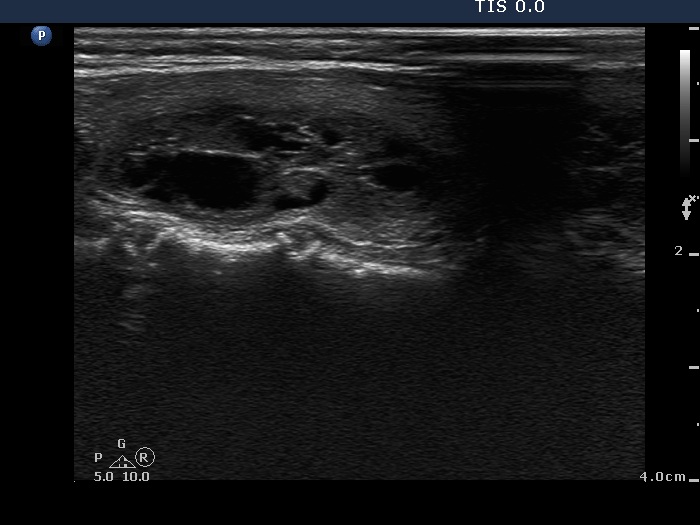

Clinical presentation: A 55-year-old woman was referred for aspiration cytology. She has a right lobectomy 10 years ago. At that time, a relatively small cystic nodule was already in the left lobe which was not operated. She noticed a lump in the left thyroid several weeks before the present examination.

Ultrasonography. There was no parenchyma in the right the thyroid bed. The left lobe was minimally hypoechogenic and had a large, multichambered cystic nodule. There were both hyperechogenic lines and granules within the dorsal wall of the cystic areas. The solid part was moderately hypoechogenic.

Comment. Most of the hyperechogenic figures correspond to posterior back wall enhancement. There were a few colloid crystals within the cystic fluid.